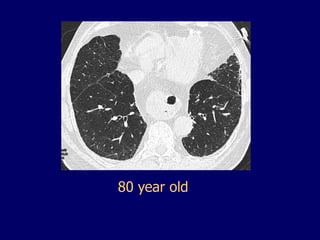

• 100.

• 101.